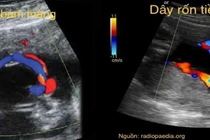

(khoahocdoisong.vn) - Phát hiện tiền sản về bất thường dây rốn qua siêu âm hiện đang trở nên phổ biến với những tiến bộ sản khoa. Siêu âm sản khoa 2 chiều, 3 và 4 chiều và Doppler như một công cụ để đo lường và đánh giá hình thái của dây rốn có giá trị trong sàng lọc đối với thai kỳ có nguy cơ cao.